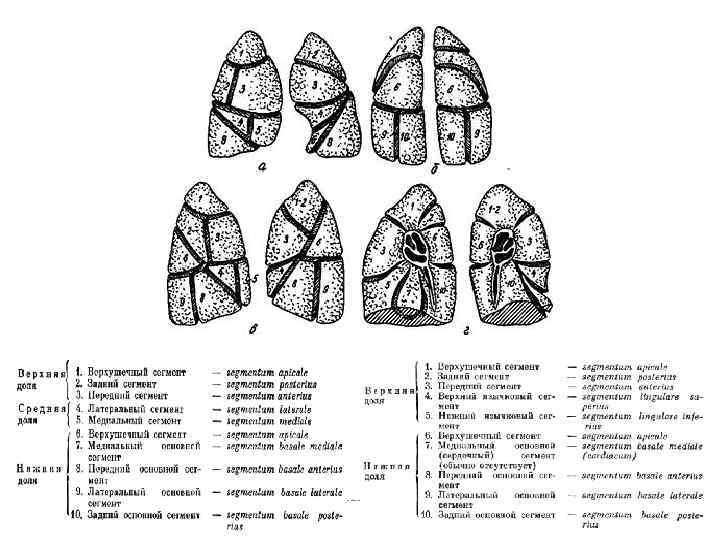

Рентгенологическая характеристика туберкулезного процесса Локализация и распространенность: в легких по долям, сегментам, а в других органах по локализации поражения. Фаза: а) инфильтрации, распада, обсеменения; б) рассасывания, уплотнения, рубцевания, обызвествления.

Рентгенологическая характеристика туберкулезного процесса Локализация и распространенность: в легких по долям, сегментам, а в других органах по локализации поражения. Фаза: а) инфильтрации, распада, обсеменения; б) рассасывания, уплотнения, рубцевания, обызвествления.